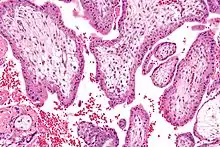

Micrografía de gran aumento de los productos de la concepción (vellosidades coriónicas).

La biopsia de corion o biopsia corial (menos conocida como muestra de vellosidades coriónicas) es un procedimiento de diagnóstico prenatal para determinar si existen cromosomopatías en el embrión. Consiste en la extracción de un pequeño trozo de corion (vellosidades coriónicas) y su análisis mediante técnicas FISH (hibridación fluorescente in situ) o PCR (reacción en cadena de la polimerasa). Se realiza habitualmente en las semanas 10-12 de embarazo, y es esta su gran ventaja con respecto a la amniocentesis, que se realiza a partir de la semana 15.